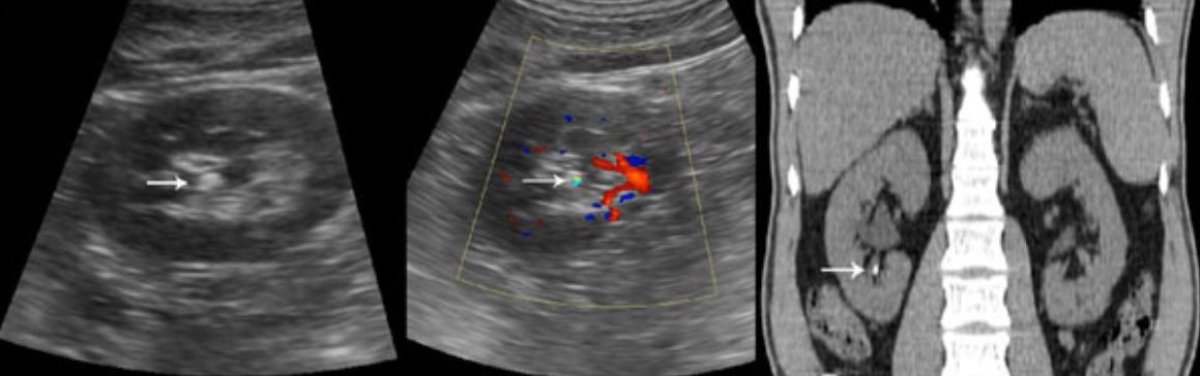

2. A Ultrassonografia (USG)

• O Problema: O ultrassom é ótimo para ver o rim e a bexiga, mas ele tem um "ponto cego" enorme: o ureter (o canal que liga o rim à bexiga). Se a pedra estiver descendo pelo meio do caminho, o ultrassom muitas vezes não consegue vê-la. Além disso, a medida do tamanho da pedra no USG é menos precisa e pode variar dependendo do médico que realiza o exame.

• Quando é útil: Para triagem inicial e para ver se o rim está inchado (hidronefrose), o que indica que algo está entupindo o canal.